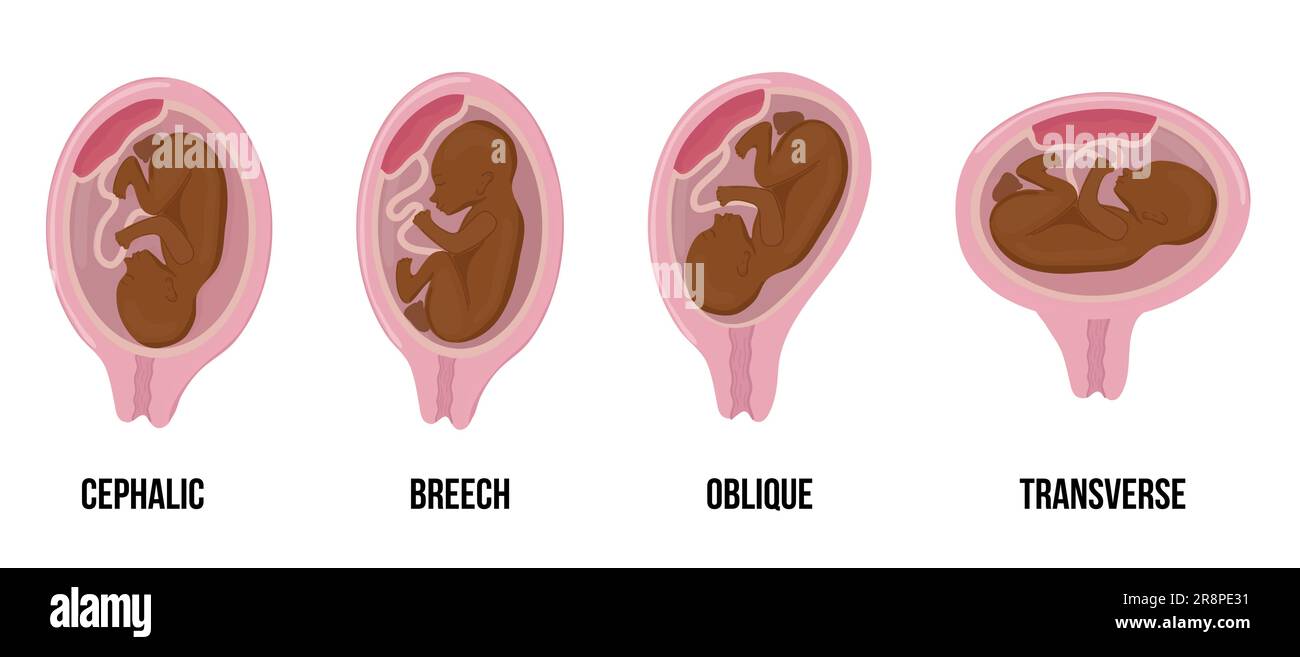

Latin arabian brown skin baby. Different wrong baby positions in uterus during pregnancy. Cephalic, Breech, transverse, Oblique lies. Colored medical Stock Vectorhttps://www.alamy.com/image-license-details/?v=1https://www.alamy.com/latin-arabian-brown-skin-baby-different-wrong-baby-positions-in-uterus-during-pregnancy-cephalic-breech-transverse-oblique-lies-colored-medical-image556116986.html

Latin arabian brown skin baby. Different wrong baby positions in uterus during pregnancy. Cephalic, Breech, transverse, Oblique lies. Colored medical Stock Vectorhttps://www.alamy.com/image-license-details/?v=1https://www.alamy.com/latin-arabian-brown-skin-baby-different-wrong-baby-positions-in-uterus-during-pregnancy-cephalic-breech-transverse-oblique-lies-colored-medical-image556116986.htmlRF2R8N8TX–Latin arabian brown skin baby. Different wrong baby positions in uterus during pregnancy. Cephalic, Breech, transverse, Oblique lies. Colored medical

Different wrong baby positions in uterus during pregnancy. Cephalic, Breech, transverse, Oblique lies. Colored medical vector illustration. Fetus with Stock Vectorhttps://www.alamy.com/image-license-details/?v=1https://www.alamy.com/different-wrong-baby-positions-in-uterus-during-pregnancy-cephalic-breech-transverse-oblique-lies-colored-medical-vector-illustration-fetus-with-image556146238.html

Different wrong baby positions in uterus during pregnancy. Cephalic, Breech, transverse, Oblique lies. Colored medical vector illustration. Fetus with Stock Vectorhttps://www.alamy.com/image-license-details/?v=1https://www.alamy.com/different-wrong-baby-positions-in-uterus-during-pregnancy-cephalic-breech-transverse-oblique-lies-colored-medical-vector-illustration-fetus-with-image556146238.htmlRF2R8PJ5J–Different wrong baby positions in uterus during pregnancy. Cephalic, Breech, transverse, Oblique lies. Colored medical vector illustration. Fetus with

African black skin baby. Different wrong baby positions in uterus during pregnancy. Cephalic, Breech, transverse, Oblique lies. Colored medical vector Stock Vectorhttps://www.alamy.com/image-license-details/?v=1https://www.alamy.com/african-black-skin-baby-different-wrong-baby-positions-in-uterus-during-pregnancy-cephalic-breech-transverse-oblique-lies-colored-medical-vector-image556143029.html

African black skin baby. Different wrong baby positions in uterus during pregnancy. Cephalic, Breech, transverse, Oblique lies. Colored medical vector Stock Vectorhttps://www.alamy.com/image-license-details/?v=1https://www.alamy.com/african-black-skin-baby-different-wrong-baby-positions-in-uterus-during-pregnancy-cephalic-breech-transverse-oblique-lies-colored-medical-vector-image556143029.htmlRF2R8PE31–African black skin baby. Different wrong baby positions in uterus during pregnancy. Cephalic, Breech, transverse, Oblique lies. Colored medical vector